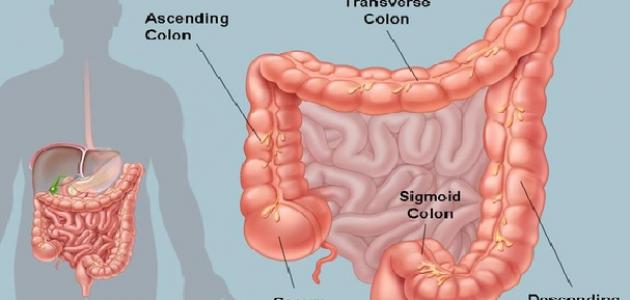

تُعرف الأمعاء الغليظة (بالإنجليزية: Large Intestine) بالقولون (بالإنجليزية: Colon)، ويُعدّ الأعور (بالإنجليزية: Cecum) أول أجزاء القولون، وهو الجزء الذي يرتبط باللفائفيّ (بالإنجليزية: Ileum) الذي يُمثّل آخر أجزاء الأمعاء الدقيقة، ويمكن القول إنّ القولون يُقسم إلى أربعة أجزاء رئيسية، وهي: القولون الصاعد (بالإنجليزية: Ascending Colon) الذي يوجد في الجزء الأيمن من البطن، والقولون المستعرض (بالإنجليزية: Transverse Colon) الذي يقطع البطن، والقولون النازل (بالإنجليزية: Descending Colon) الذي يمثل الجزء الأيسر من البطن، والقولون السينيّ (بالإنجليزية: Sigmoid colon) الذي يقع قبل المستقيم (بالإنجليزية: Rectum) تماماً. وتكمن وظيفة القولون في تصنيع البراز وإنتاجه، وذلك بسحب الماء، والأملاح، وبعض العناصر الغذائية، ومن الجدير بالذكر أنّ هناك مليارات البكتيريا الموجودة في القولون والتي تظلّ في مستوياتٍ تُبقيها متوازنة مع وضع الجسم وحاجته، وتُبطّن القولون مجموعة من العضلات التي تدفع البراز المتكوّن إلى الأجزاء السفلى.[١]